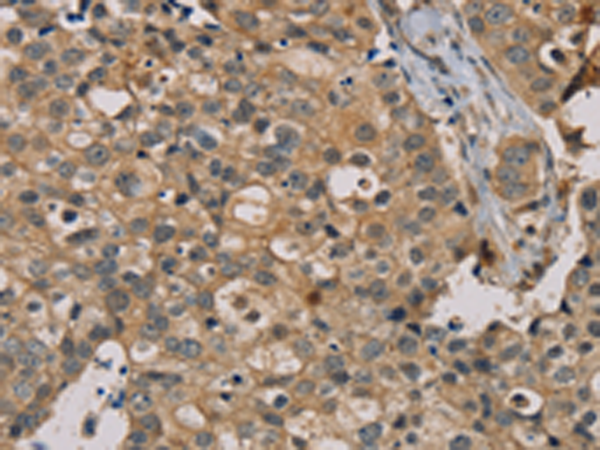

分类: 科研抗体货号: P08529别名: ZRF; MTF-1应用: IHC反应种属: Human